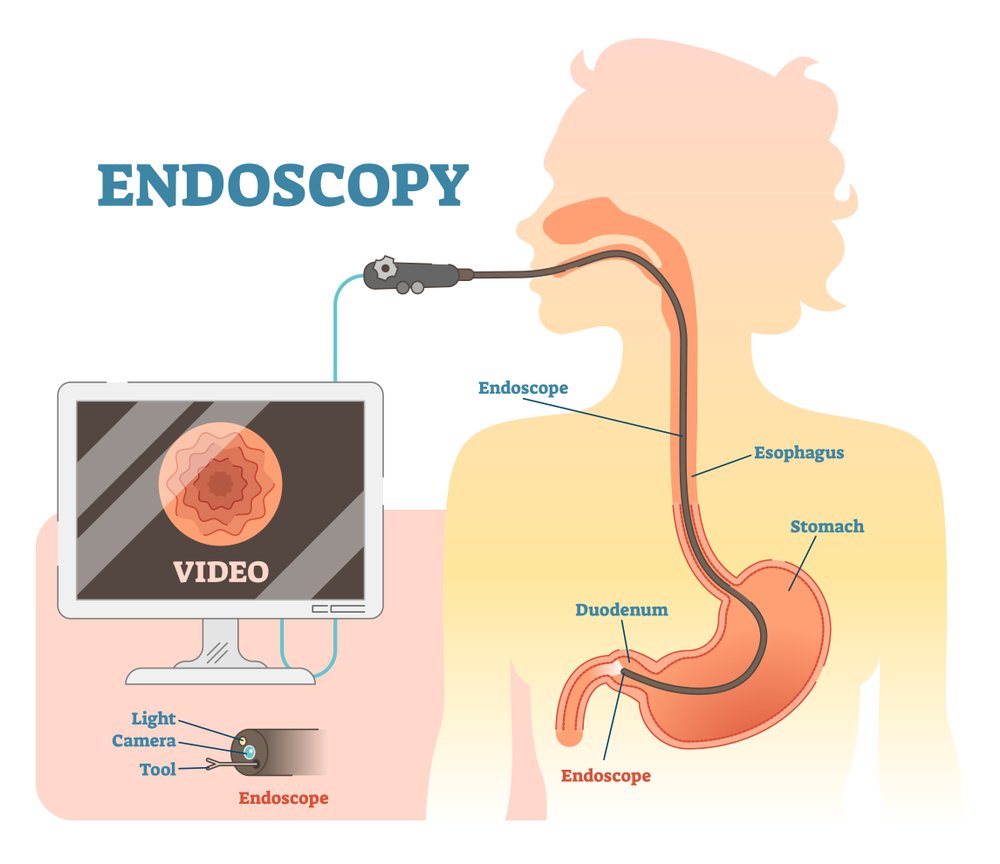

Upper GI endoscopy is a procedure to evaluate the mucosa of esophagus, stomach and duodenum. Endoscope is introduced by the mouth after sedation, mucosal appearance of esophagus, stomach and duodenum is evaluated and biopsy can be taken from suspicious areas, and endotherapy can be done for the bleeding lesions.